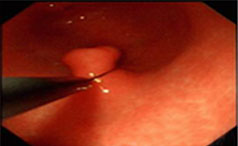

一般来说胃息肉的患者没有太多典型的症状表现,但是随着疾病的逐步发展或严重,胃息肉的患者可能会出现食欲减退、消化不良、胃部疼痛、恶心呕吐、腹胀......【详情】

常见症状:上腹隐痛、腹胀、不适

无痛性便血、脱垂

【导语】胃息肉的存在会干扰胃的正常消化功能,从而导致消化不良症状的出......【详情】